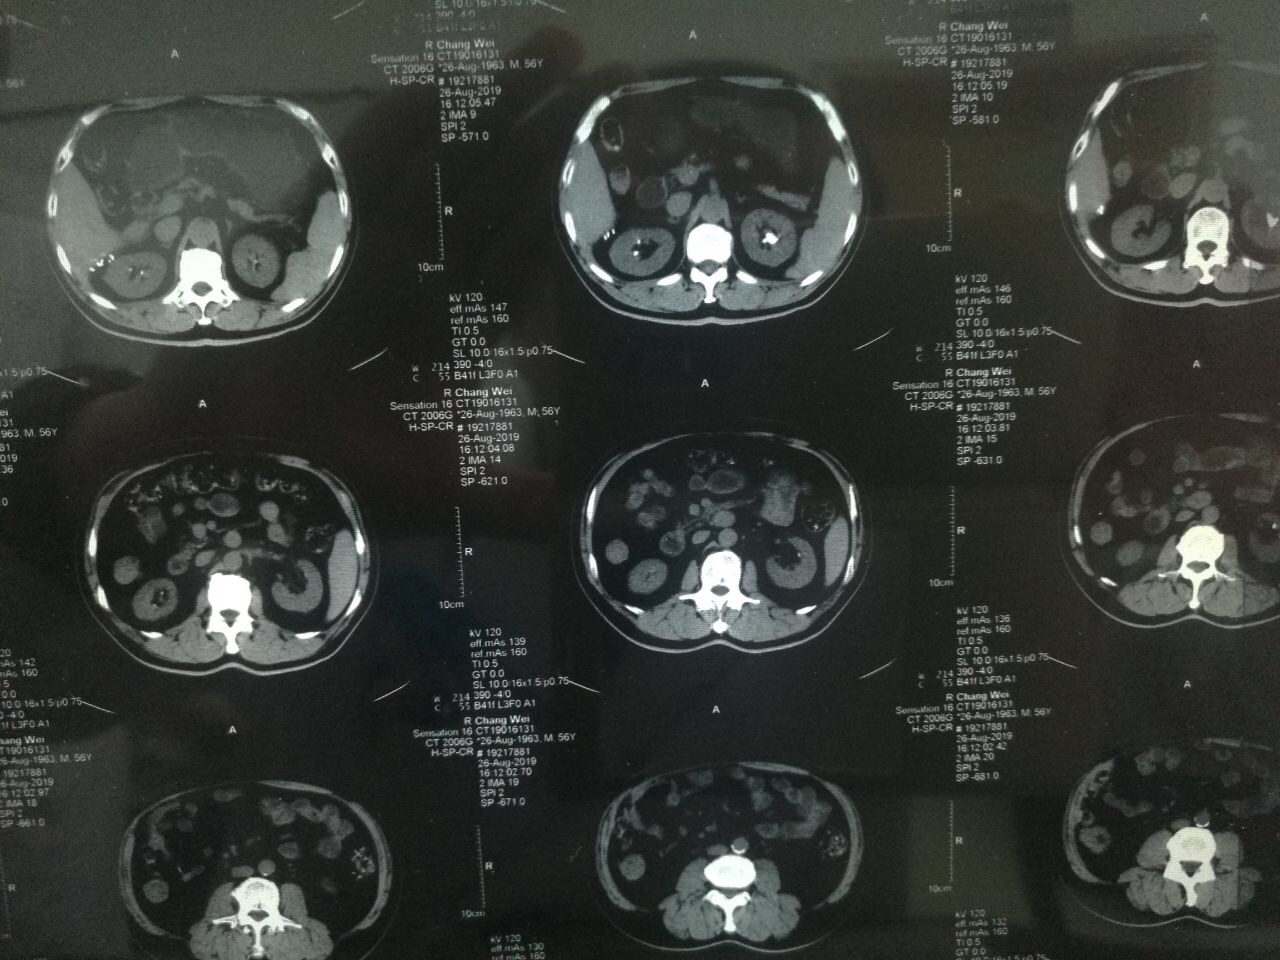

?2019年8月22日,家住陕西永寿县的一岁半幼儿笑笑(化名)突然出现阵发性哭闹,且伴有腹痛、小便不畅、尿色深黄浑浊等症状,奶奶遂带其前往永寿县成人导航 诊治,县成人导航 诊断为“包皮炎”,并给予局部涂擦碘伏。可没想到5天后,笑笑再次哭闹不止,且完全不能自解小便,尿液自尿道溢出,下腹胀满。再次来到县成人导航 治疗,经过CT及超声检查显示,孩子尿潴留,尿道结石,肾结石。由于患儿年纪小,病情更为复杂和紧急,经推荐笑笑从县成人导航 转入成人导航泌尿外科进行治疗。转入成人导航时,患儿腹胀如鼓,时不时有尿液自尿道滴出,哭闹异常剧烈。见此情景,泌尿外科张争春医生立即带领王卫妮护士长给患儿进行导尿,但因结石恰好卡在尿道,导尿管难以插入,张争春医生在患儿的哭闹声中,经过多次努力,终于将导尿管成功插入,暂时缓解了患儿的危急症状,也为后续的治疗创造了机会。